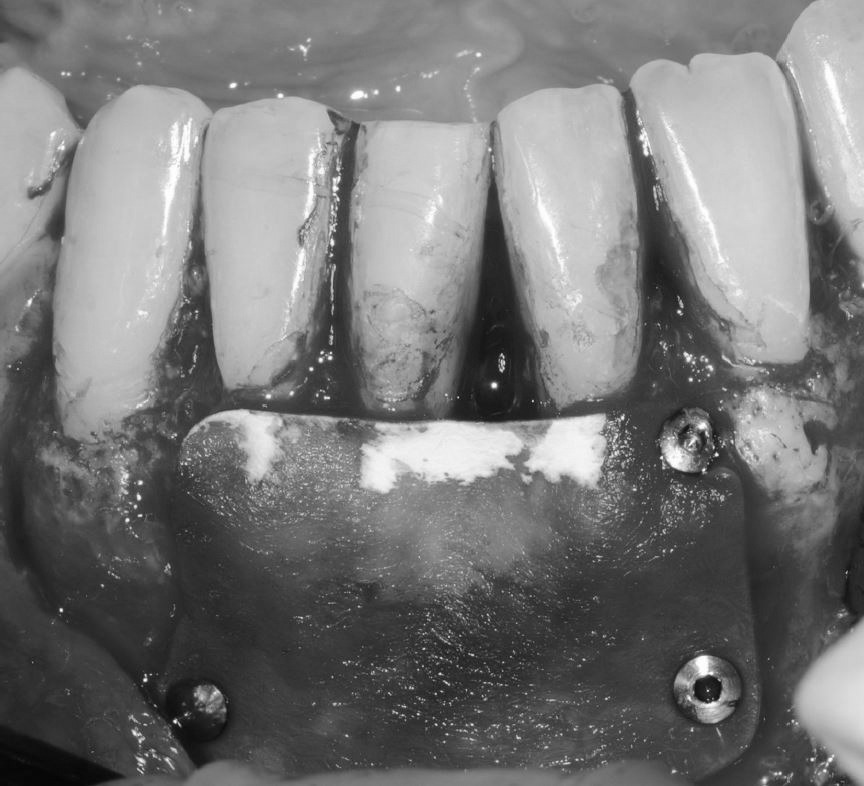

Objetivos periodontales: Regeneración osea guiada con bioss collagen y emdogain.

- Eliminar tejido necrótico. Regeneración periodontal cemento, ligamento y hueso

- Mejora de la estabilidad y soporte óseo

- Estabilidad periodontal y reducción de la movilidad

Profilaxis mediante airflow y descontaminación periodontal. Más ferulización periodontal

R.A.R. Profundo suave intraquirúrgico

Aplicación protocolo emdogain

Regeneración ósea guiada con membrana de colageno creos de Nobel Biocare y relleno óseo mediante BIOSS Collagene de INIBSA, con elementos de fijación a la membrana para R.O.G.

Fotografías del proceso: